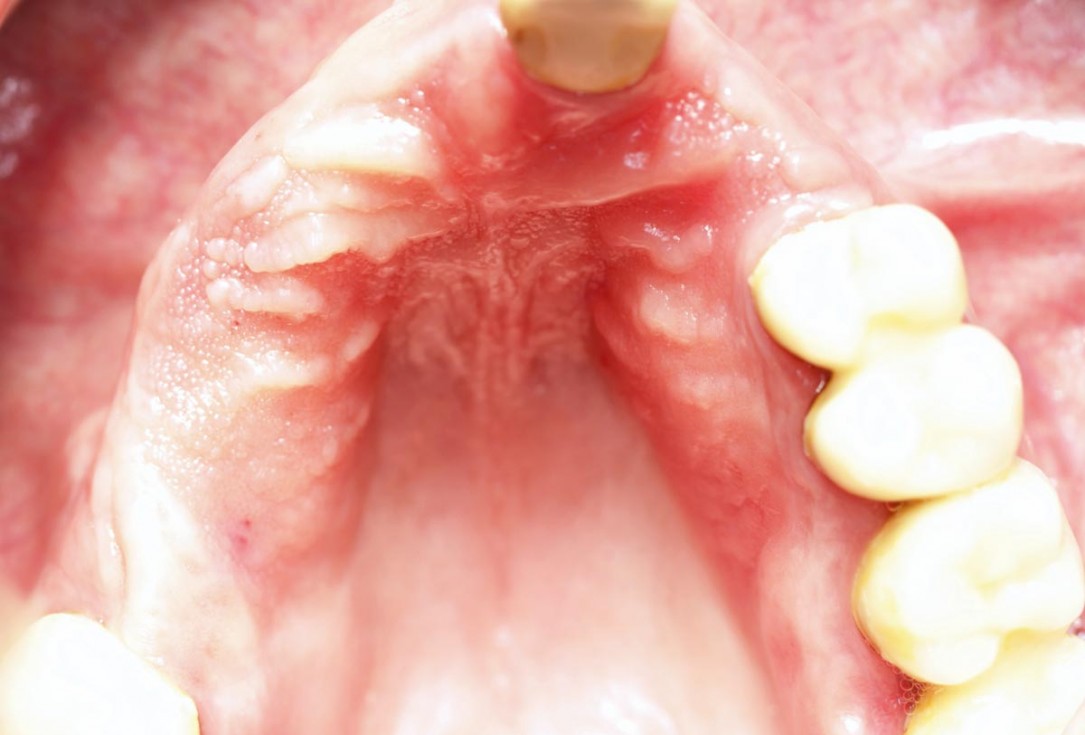

Preoperative situation – Maxillary defect in area 14-16 (loss of implant 16 due to periimplantitis, tooth 14 extracted recently and area 15 already edentulous for a while)